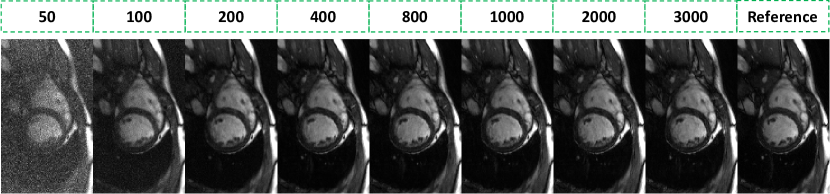

The ablation study evaluated the effectiveness of the proposed temporal guidance priors, including - and - priors, by analyzing results with different weighting factors and from Eq. (22) on cardiac cine data, as presented in Supporting Information Figure S3. The influence of the number of reverse diffusion steps on reconstruction fidelity and computational runtime was analyzed on cardiac cine data, as depicted in Supporting Information Figure S4. Additionally, the impact of incorporating the CG module during inference was assessed on dynamic lung data, with results shown in Supporting Information Figure S5.

The diffusion modeling-based methods also have limitations. One notable limitation of dDiMo is its relatively slow inference speed, which stems from the sequential nature of the diffusion modeling process. Compared to other deep learning methods where reconstruction can be conducted by running the network once, the reverse diffusion requires the iterative operation of network inference for extensive steps, in our case, 1000 steps. Supporting Information Figure S5 highlights the trade-off between the number of reverse diffusion steps and reconstruction quality. Reconstructions with fewer than 100 steps exhibit residual noise while increasing the number of steps enhances detail recovery and noise suppression. In our study, 1000 reverse diffusion steps were employed, balancing reconstruction accuracy and computational efficiency. However, this leads to an average inference time of 6 minutes for reconstructing one image volume. To address this challenge, future research could leverage the potential of latent diffusion models, as highlighted in recent advancements [65]. By redefining the diffusion process in a compressed latent space rather than the pixel space, these models significantly reduce computational complexity while maintaining the ability to generate high-quality data restoration. Additionally, future work could explore integrating other temporal feature-aware and efficient data compression techniques, such as subspace learning [39, 66], into diffusion modeling to alleviate the current high computational burden.

Figure S4. Quality assessment results of dDiMo at 4 acceleration with varying total reverse diffusion steps during inference. Increasing the total diffusion steps improves the reconstructed images by enhancing sharpness and detail restoration. For the experiments presented in the main manuscript, 1000 diffusion steps were used, providing a balance between image quality and inference time efficiency.